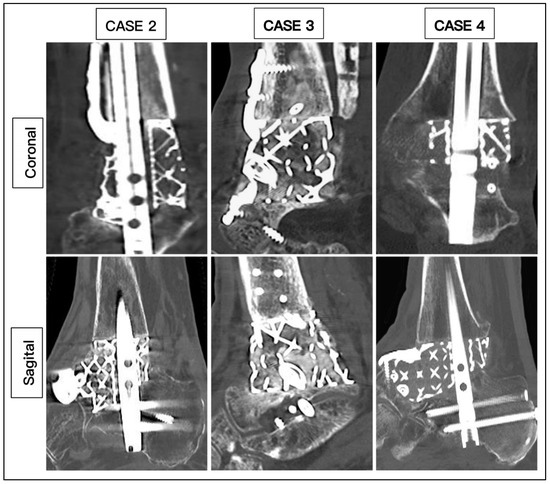

2.2. Surgical Technique

| Modification | Tibial and Navicular Flange, Nail | Navicular Flange, Nail | Tibial and Navicular Flange | Navicular Flange, Nail | Nail | Articulating Navicular Extension, Tibial Flange, Nail |